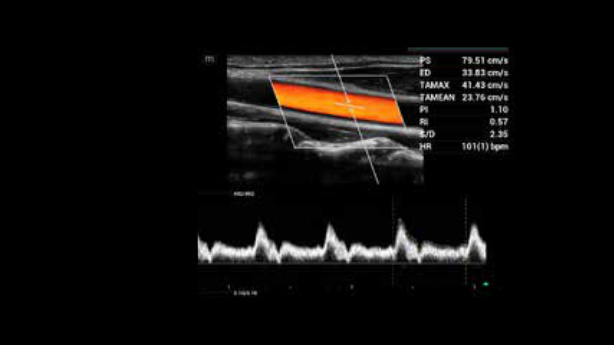

EcĂłgrafo Zeus presenta una interfaz fĂĄcil de usar y funciones sencillas para realizar exploraciones eficientes. Sus versĂĄtiles capacidades abarcan la ecografĂa abdominal, vascular, de partes peque?as y musculoesquelĂ©tica, lo que aumenta la confianza en el diagnĂłstico.